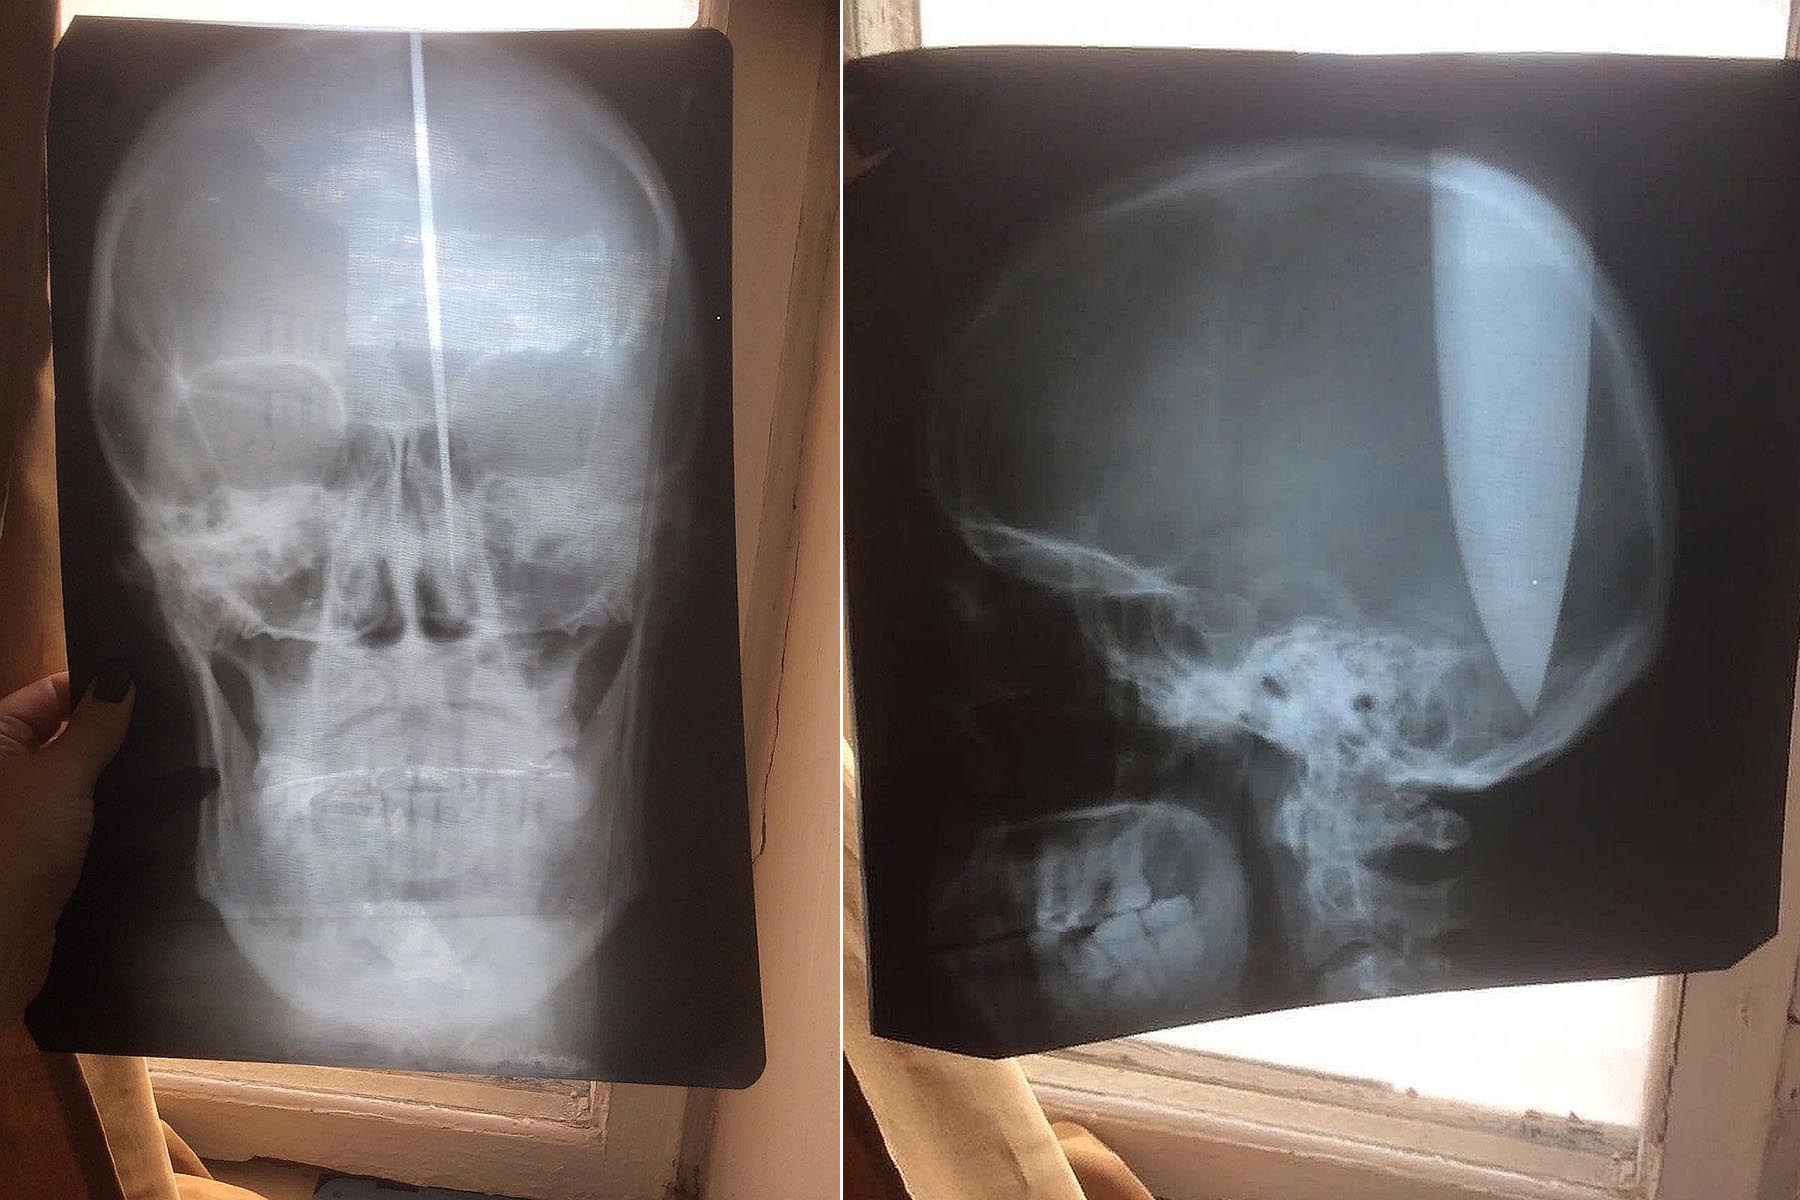

Psychicky narušený muž si do lebky zabodl dlouhý nůž: Nemohl prý dýchat